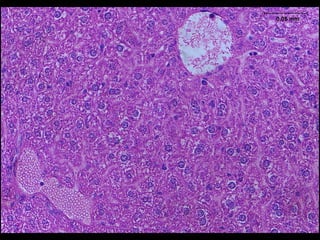

Section of the kidney of a pig fed on diet containing 800 ppb OTAfor

6 months. HE, ×300. Karyomegaly and slight granular degeneration in the

epithelium of proximal tubules.

6 months. HE, ×260. Vacuolar degeneration in the epithelium of some

proximal tubules.